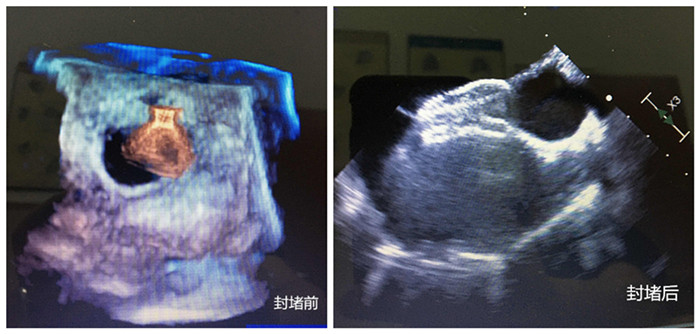

無(wú)影燈下,主刀醫(yī)生周珉在小強(qiáng)的右腋下切了一個(gè)長(zhǎng)度為4cm左右的切口,隨后,在經(jīng)食管探頭的引導(dǎo)下,封堵器順利通過心臟缺損部位,完成釋放和固定,牢牢地堵住缺口,“心臟正常的血液循環(huán)途徑恢復(fù)!”僅30分鐘,小強(qiáng)的心臟修補(bǔ)成功。

封堵前、封堵后兩張圖

守在手術(shù)室外的家人表示難以置信。三天后,小強(qiáng)便順利出院。